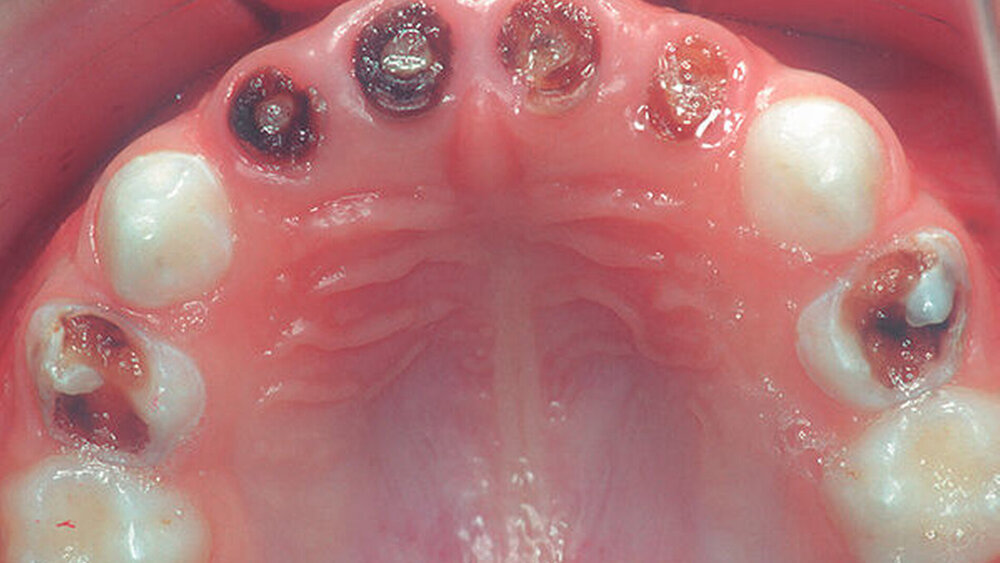

Die vorliegende Untersuchung befasst sich ausschließlich mit Kindern, die unter ECC leiden und bei denen aufgrund ihres hohen Behandlungsbedarfs eine Zahnsanierung unter Narkose durchgeführt werden musste. Das Hauptziel der Studie war es, mehr über die Zusammenhänge der unterschiedlichen Risikoindikatoren innerhalb dieser exponierten Gruppe zu erfahren, um künftig durch das Weglassen eines oder mehrerer Faktoren die Entstehung bzw. das Wiederauftreten kariöser Läsionen bei diesen Kindern und bei anderen Klein- und Vorschulkindern positiv zu beeinflussen.

Der durchschnittliche dmft-Wert lag bei 9,49 (SD: 3,51), der durchschnittliche dmfs-Wert bei 26,35 (SD: 15,18). Zwischen den Geschlechtern zeigte sich in Bezug auf den Kariesindex kein statistisch signifikanter Unterschied (p>0,05; t-Test).

Ergebnisse der vorliegenden Studie stützen sich auf eine spezielle Gruppe, nämlich Kinder mit hohem Behandlungsbedarf aus der Region Basel. Im Durchschnitt waren die Hälfte der Milchzähne und ein Drittel der Milchzahnoberflächen von Karies betroffen. Das Hauptziel der Studie war es, Risikoindikatoren und deren mögliche Zusammenhänge zu ermitteln, die das Auftreten kariöser Läsionen begünstigen. Die Auswertung der standardisierten Elterninterviews ergab, dass neben den bereits aus vorherigen Studien aus der Schweiz bekannten Faktoren (Herkunftsland der Mutter, hoher Konsum zuckerhaltiger Getränke) vor allem der Putzbeginn und das fehlende Nachputzen Risikoindikatoren darstellen.